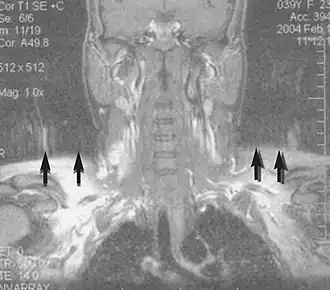

Angiografie

Rezonantele magnetice (MRA) generează imagini ale arterelor pentru a le evalua pentru stenoză (îngustare anormală) sau anevrisme (dilatări ale peretelui vascular, expuse riscului ruperii). MRA este adesea folosit pentru a evalua arterele gâtului și creierului, aorta toracică și abdominală, arterele renale și picioarele (numită "run-off"). O varietate de tehnici pot fi utilizate pentru generarea imaginilor, cum ar fi administrarea unui agent de contrast paramagnetic (gadoliniu) sau folosind o tehnică cunoscută sub denumirea de "îmbunătățire în legătură cu fluxul" (de exemplu, secvențe 2D și 3D de timp de zbor) cea mai mare parte a semnalului de pe o imagine se datorează sângelui care sa mutat recent în acel avion (vezi, de asemenea, RMN FLASH). Tehnicile care implică acumularea de faze (cunoscute sub numele de angiografie cu contrast de fază) pot fi, de asemenea, folosite pentru a genera hărți ale vitezei de curgere cu ușurință și cu precizie. Rezonanța cu rezonanță magnetică (MRV) este o procedură similară utilizată pentru a imagina vene. În această metodă, țesutul este acum excitat inferior, în timp ce semnalul este adunat în planul imediat superior celui de excitație - imaginând astfel sângele venos care sa mutat recent de pe planul excitat.